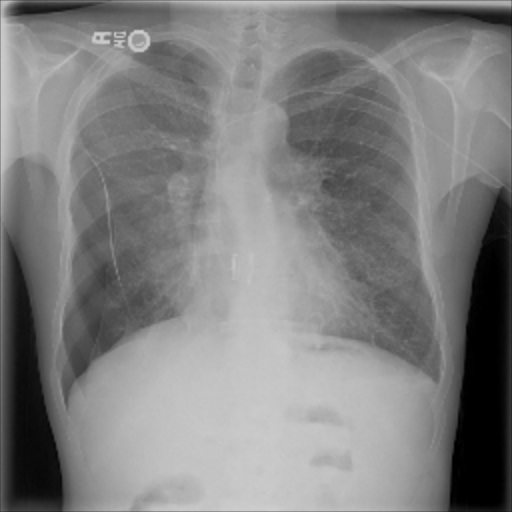

The data used in the following experiments consists of DICOM X-ray images, obtained from the University of Washington Medical Center and affiliated institutions, centered in Seattle by scanning radiology reports from the last three years. Inclusion criteria were: (i) Digital Radiography (DR) images, (ii) Chest radiographs, (iii) Posterior-anterior or anterior-posterior view position, (iv) Adult patients. Any personal health information was removed. Image-level labels were derived from natural-language processing based analysis of the reports. Cases were partially reviewed by a radiologist to confirm appropriate finding in the report’s impression section and this represented a critical finding. The resulting dataset contained 1003 images: 437 with pneumothorax, 566 with a different or no abnormality detected. We generated pixel-level annotations of the pneumothorax region for 305 of the positive cases. For training and evaluation, we divided the dataset into five cross-validation splits of similar size, such that images of the same patient resided in the same split.

The pre-trained ResNet-50 was also employed as the patch-level classifier within the MIL approach. We chose the binary cross-entropy between the maximum patch score and the image-level label as the loss function. The batch size was selected as the number of patches per image. We trained with an initial LR of for 30 epochs and achieved an average AUC of 0.930.01 using this method. High patch scores (indicated by thicker red frames, cf. Fig. 5(c)) give a hint on the location of the pneumothorax.

As pixel-level ground truth annotations were available only for a subset of the images, 871 images in total were used for training the FCN for 400 epochs. As a loss function, a weighted cross entropy (25.0 for pneumothorax pixels and 0.5 for non-pneumothorax pixels in order to account for the smaller size of pneumothorax regions) was employed at pixel-level with an initial LR of . With an average AUC of 0.920.02, the overall performance of this method is worse than the CNN and MIL. On the other hand, the FCN generates pixel-level probabilities (cf. Fig. 5(d)), which indicate the location of the pneumothorax. The average Dice coefficient for positively classified cases is .